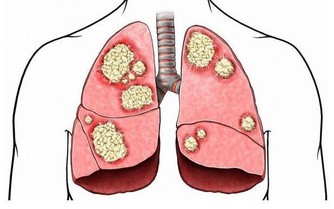

香菜中含有的黃酮類、多種維生素和微量元素等物質,具有抗癌、護腎、降血糖等作用。